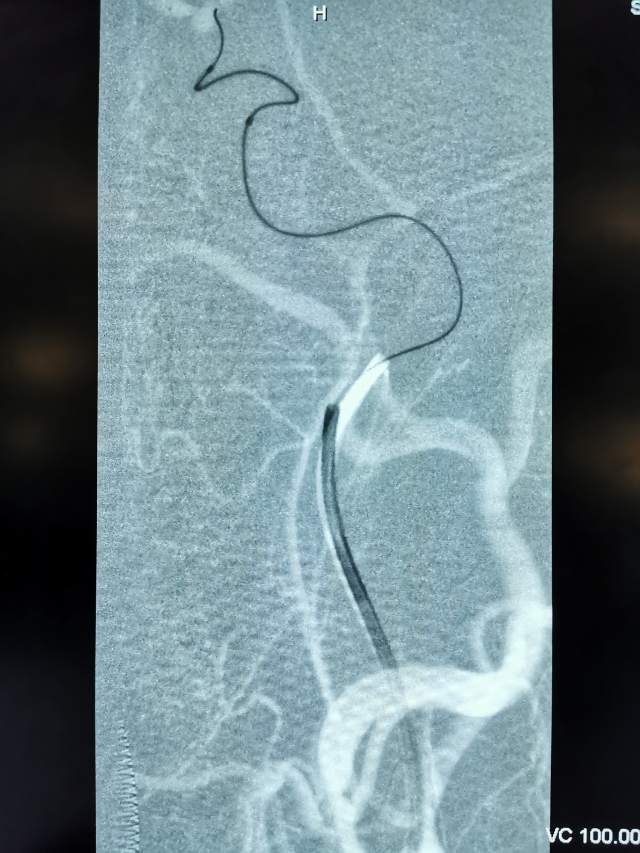

今日,我们重新为患者开通闭塞的血管,术后,患者重新焕发勃勃生机,俨然换了一个人~~~

一个月后根据复查情况酌情给予二期支架植入